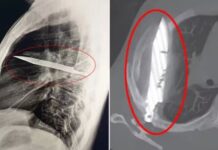

Homem descobre que tem f4c4 alojada no peito após oito anos

Aos 44 anos, um homem foi ao médico e descobriu que vivia com uma faca alojada em seu peito por pelo menos oito anos...